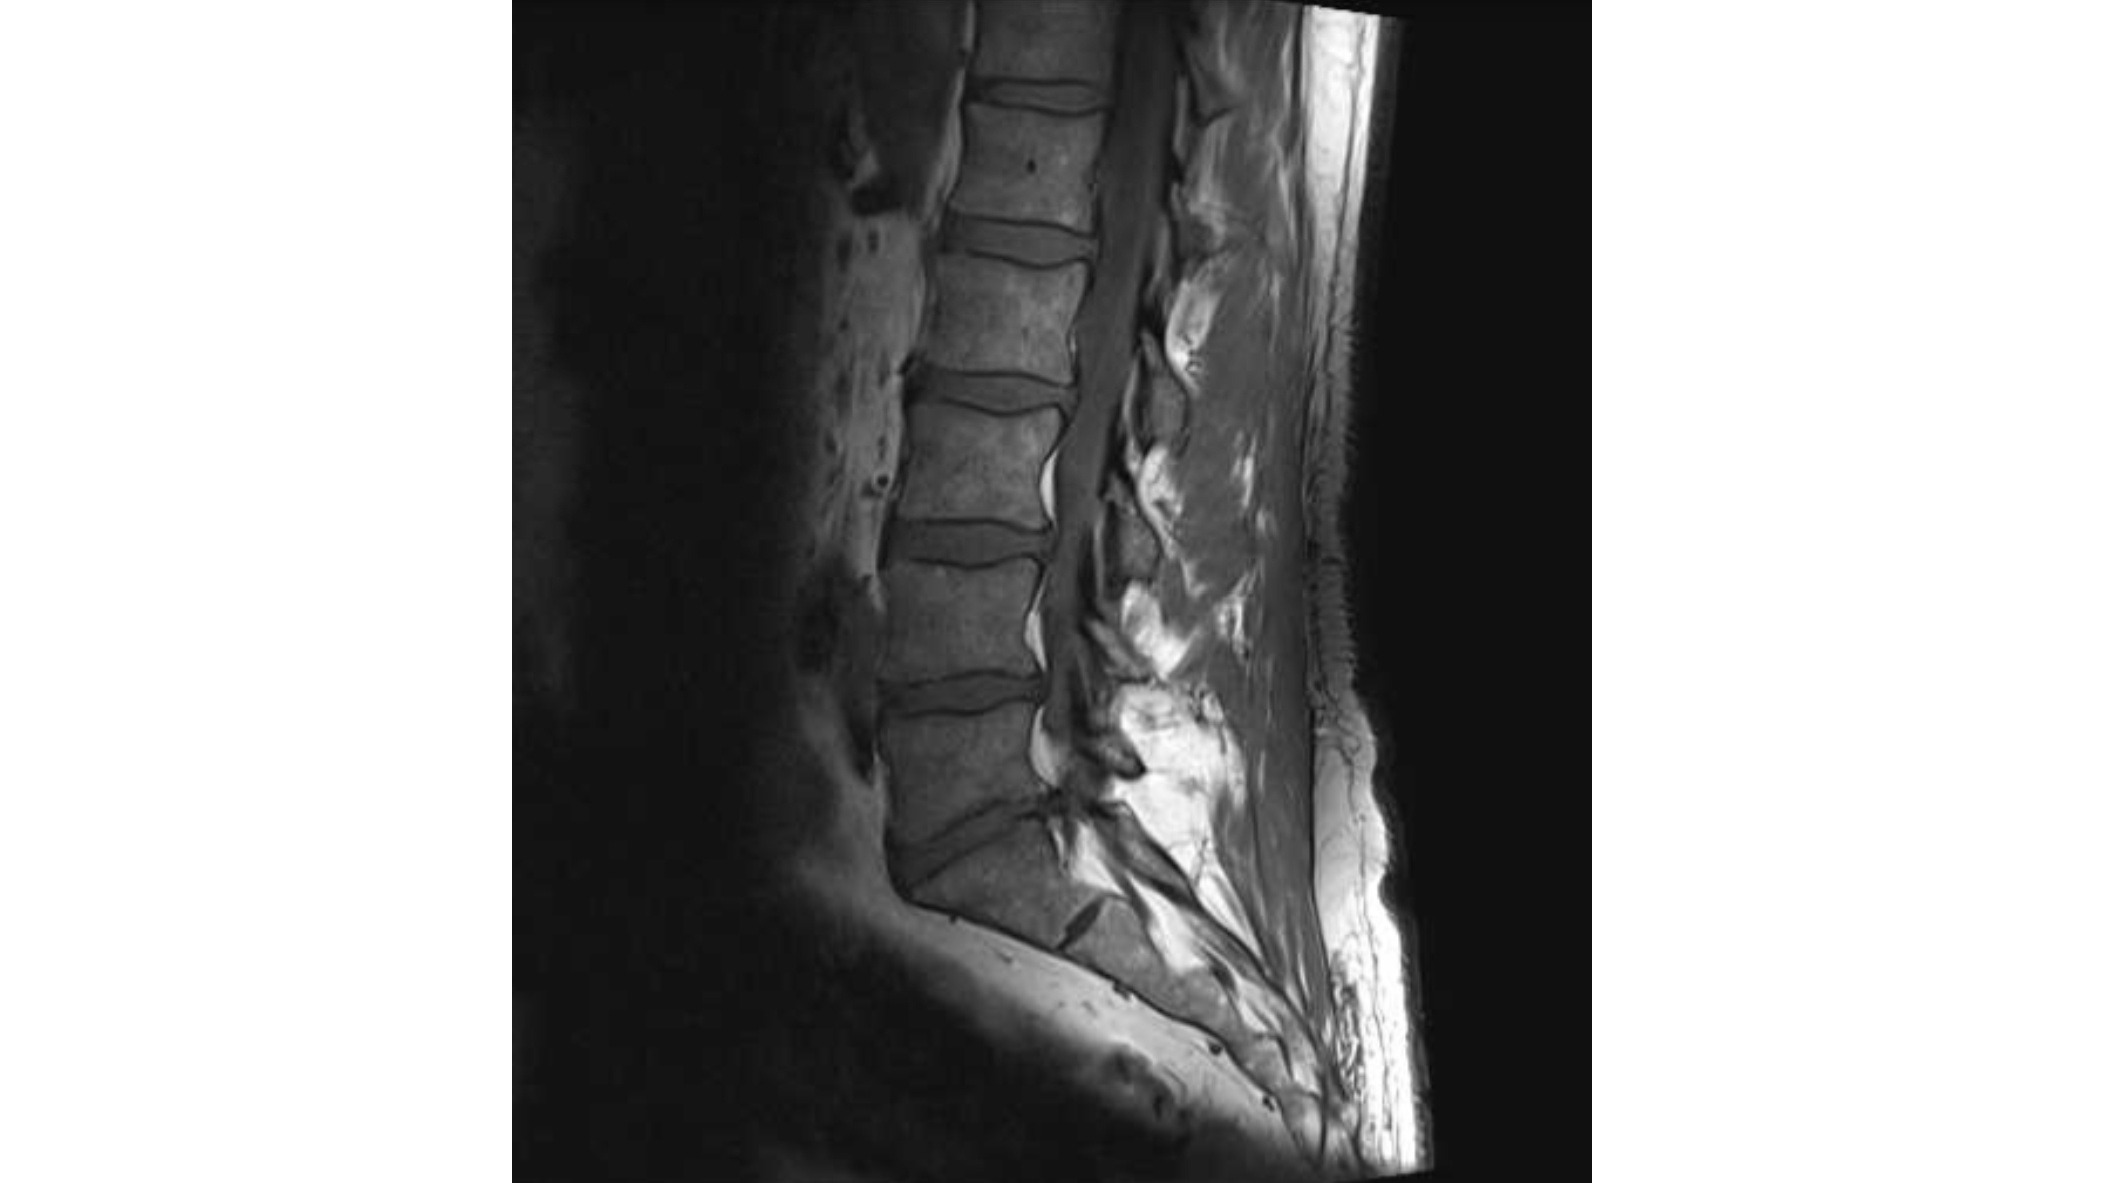

Multiple disc replacement spinal surgery

I'm Kevin, my friends call me Kev. I'm 49 years young. I'm a self employed knife maker/teacher. I have suffered chronic pain for 30 years following an injury to my lower back and over the last 18 months or so things have become progressively worse. I've been unable to work a full day let alone teach and because of the nature of my injury it's affected me financially and emotionally. I have the opportunity to get major surgery to give me stability and significantly reduce the pain I'm experiencing as well as giving me a new lease on life. I'll be out of action for up to 12 months following as I go through the recovery process. I've never reached out for help but I'm comfortable doing so with this. I injured my back 30 years ago and don't know a life without pain and uncertainty, this operation is an opportunity to start again. Better late than never. Along with the costs associated with the surgery and recovery I'll donate to a local organisation that deals with suicide prevention and mental health services. They helped me a lot and I'd like to give something back. In return I can only offer my sincerest gratitude for your help. I hope this is enough. Regards, Kev